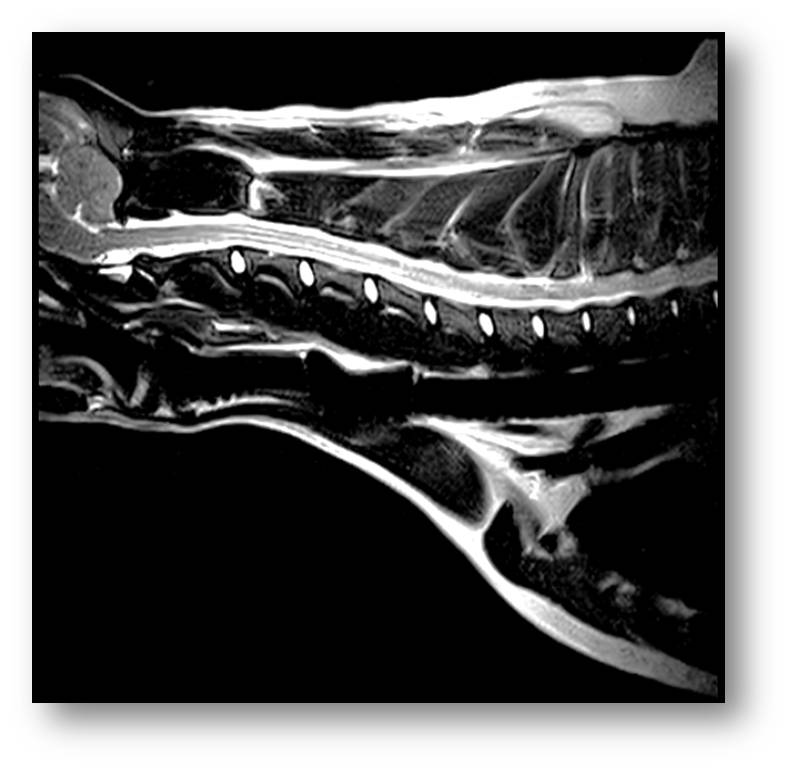

EXCELLENT image quality

"We had to find a way to provide excellent care for our patients. I believe that the Magnus veterinary specific MRI is the best way to do this.  In fact, the Magnus MRI provides similar image quality to high field MRI with much less cost to the practice and the environment.  I couldn't be happier with this new MRI.  The fact that this new unit will be able to perform MRI Guided Microwave Ablation means the Magnus was just elevated to the next level as a diagnostic tool and advanced treatment system."                              Roger M. Clemmons, DVM, PhD, DACVIM (Neurology)

Here is how it works: An MRI is performed to find the exact location of the tumor. The doctor then guides a needle to the tumor while watching the real time MRI images on the monitor. The MRI ensures that the needle is perfectly placed in the tumor. By applying up to 300 GHz of microwave power the tumor is ablated. While the tumor is being ablated, the intratumoral temperature is constantly monitored to prevent damage to the surrounding tissue.